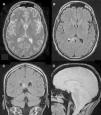

ResultadosEn las secuencias T2, FLAIR y EGRT2* se visualizan las LAD de manera adecuada en más del 80% de los casos. En FLAIR se visualizan mejor las LAD hemisféricas a nivel subcortical y el EGRT2* resalta las LAD hemorrágicas. En nuestra serie hemos visto que el grado de concordancia para diagnosticar LAD entre las secuencias T2, FLAIR y EGRT2* es alto (0,8). La secuencia T2 es la que tuvo un valor más alto en las curvas ROC tanto en la clasificación de Gentry (0,68; IC 95%: 0,61-0,76; p<0,001, Nagerlkerke-R2 0,26) como en la de Firsching (0,64; IC 95%: 0,57-0,72; p<0,001, Nagerlkerke-R2 0,19), seguida de la secuencia FLAIR y de la EGRT2*. Se observó, tras realizar un análisis multivariable, que las clasificaciones de Gentry y Firsching determinadas de forma independiente en cada secuencia se relacionaban con el pronóstico final de los enfermos al año del traumatismo (p<0,02).

ResultsTAI lesions were adequately visualized on T2, FLAIR and GRET2* sequences in more than 80% of the studies. Subcortical TAI lesions were well on FLAIR and GRET2* sequences visualized hemorrhagic TAI lesions. We saw that these MR sequences had a high inter-rater agreement for TAI diagnosis (0.8). T2 sequence presented the highest value on ROC curve in Gentry (0.68, 95%CI: 0.61-0.76, p<0.001, Nagerlkerke-R2 0.26) and Firsching classifications (0.64, 95%CI 0.57-0.72, p<0.001, Nagerlkerke-R2 0.19), followed by FLAIR and GRET2* sequences. Both classifications determined by each of these sequences were associated with poor outcome after performing a multivariable analyses adjusted for prognostic factors (p<0.02).